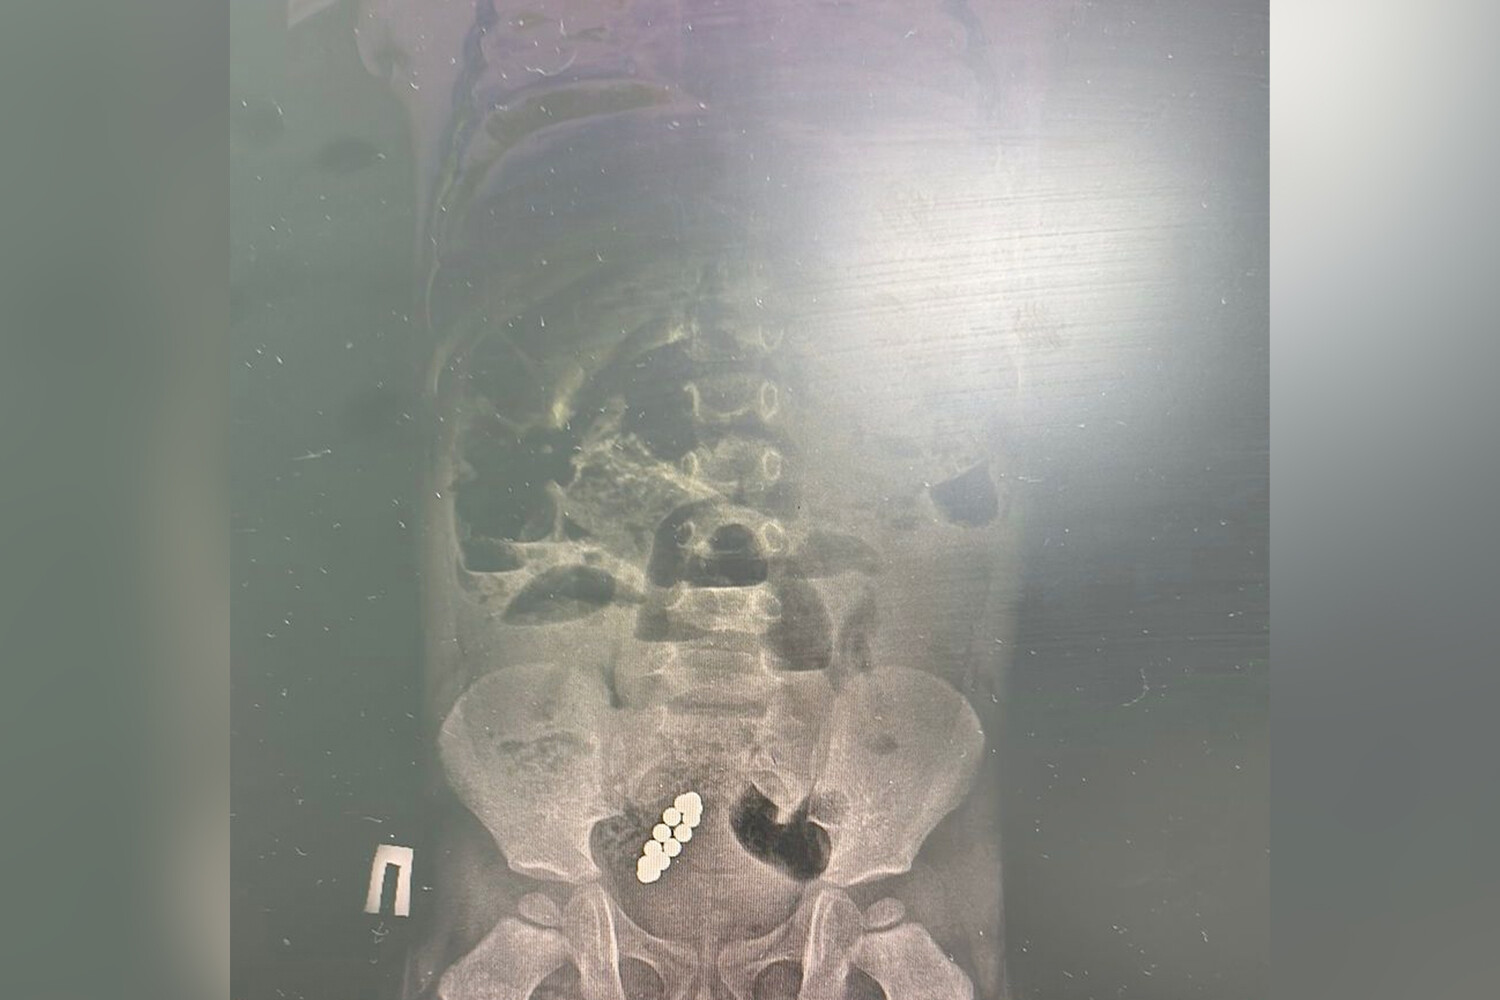

Тянули с больницей: ребенок жил с 13 магнитами в ЖКТ девять дней

В Казахстане спали ребенка с 13 магнитами в кишечнике, он жил с ними девять дней

Врачи Центра детской и неотложной помощи в Алматы (Казахстан) спасли семилетнего ребенка, который больше недели проходил с 13 магнитами в кишечнике. Об этом сообщили в пресс-службе медицинского учреждения.

По информации врачей, мальчик почувствовал недомогание 27 января. Родители отвезли сына в частную клинику, где на рентгене увидели магниты и рекомендовали обратиться в больницу. Но родители приняли решение «наблюдать за состоянием ребенка самостоятельно» и повторно показали сына врачам через девять дней, когда у него началась рвота до 15 раз в день. Мальчика экстренно госпитализировали в Центр неотложной помощи.

«Диагноз – острая низкая кишечная непроходимость и инородное тело в желудочно-кишечном тракте. Нам пришлось выполнить две сложные операции», — рассказал хирург медучреждения, добавив, что из кишечника мальчика удалили 13 магнитов.